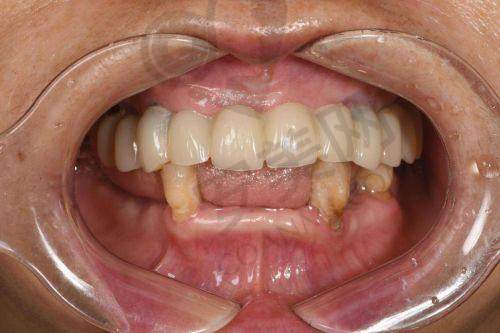

经过一段时间的修复,我的全口牙齿种植成效终于显现出来了。现在,我的牙齿看起来非常自然,和真牙几乎没有区别。而且,牙齿的咀嚼功能也得到了较大的修复,我可以像以前一样正常地吃饭了。这让我感到非常开心,生活质量也得到了较大的提高。

更重要的是,因为牙齿问题得到了解决,我变得更加自信了。以前因为牙齿缺失,我不敢大声说话、不敢笑,现在这些顾虑都没有了。我可以尽情地享受生活,和朋友们交流也更加自在了。